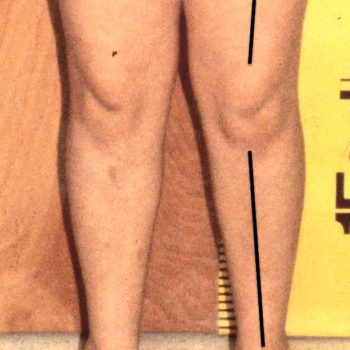

Valgus Great Toe Hallux

Note what signs you see.

I (W. Wertelecki, M.D.) see that the axis of the great toe (hallux) is deviated away from the midline of the body (valgus).

Hallux valgus is an acquired deformity relatively more common in women. In vernacular parlance it is called bunion.

PERSPECTIVE: There is a wide-held belief that one of the causes of hallux valgus is the wearing of narrow-pointed shoes. Regarding valgus, cubitus valgus (forearm) and genu valgus (knee) are important signs that can be signals of important syndromes (see).